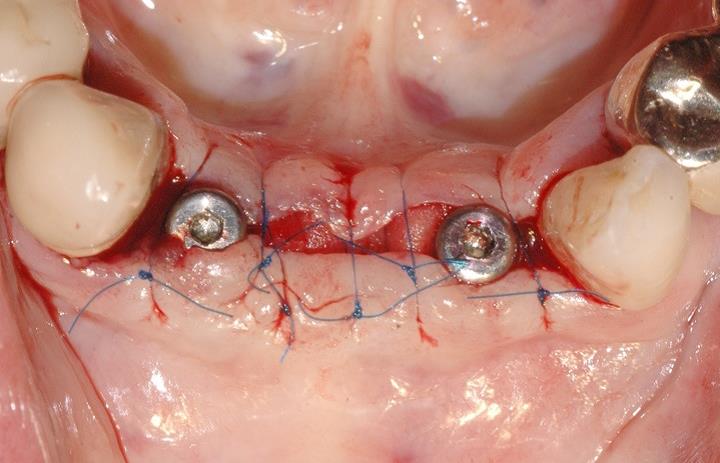

7/15 - Tension-free wound closure with different suturesSoft tissue augmentation and GBR with mucoderm® and maxresorb® - Dr. S. Scherg